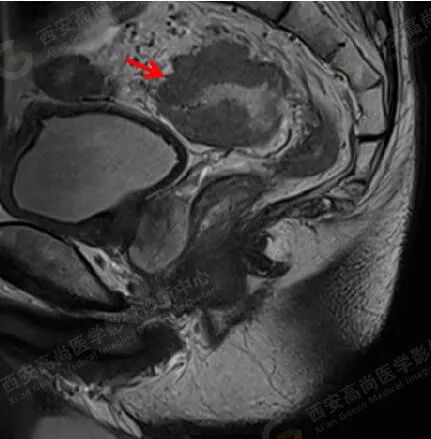

男,60 岁,便血一月余,发现直肠肿块一周。

MR 平扫+DWI: 直肠上段、乙状结肠肠壁不均匀增厚,最厚处约 2.5 cm,病灶长约 5.3 cm,边缘欠清晰,相应肠腔狭窄,病灶呈团块状稍长 T1 稍短 T2 信号,压脂像上呈稍高信号,DWI 像上呈高信号,ADC 图上呈稍低信号。

直肠上段、乙状结肠占位,符合肠 Ca 表现。